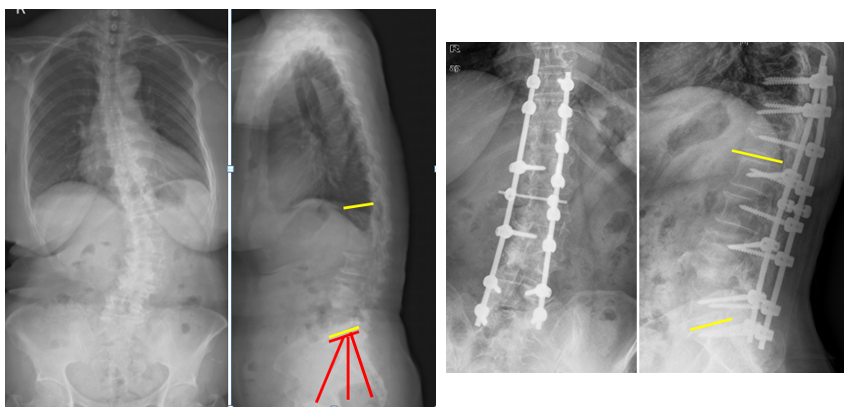

图5 脊柱远端融合节段越多,如包括L5-S1水平固定到骶骨或髂骨,发生交界性后凸的可能性越大

(2)上固定椎在交界区或存在交界性后凸

图6 长节段融合固定上固定椎(UIV)选择在胸10-12胸腰椎交界区是PJK的风险因素之一

图7 术前-术后1个月-术后1个月外观